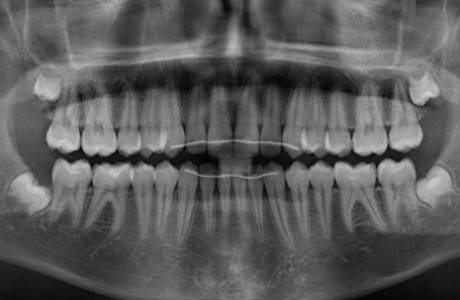

До лечения

Подросток 12 лет. Глубокий прикус, выраженный дефицит места для верхних клыков и премоляров внизу.Смещение средней линии зубов. Жалобы – «не прорезываются зубы»